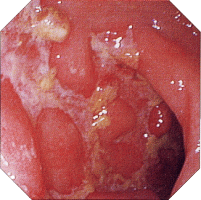

内視鏡所見

初期病変 アフタ様びらん アフタ様潰瘍

クローン病 クローン病画像 クローン病画像

提供:牧山和也先生